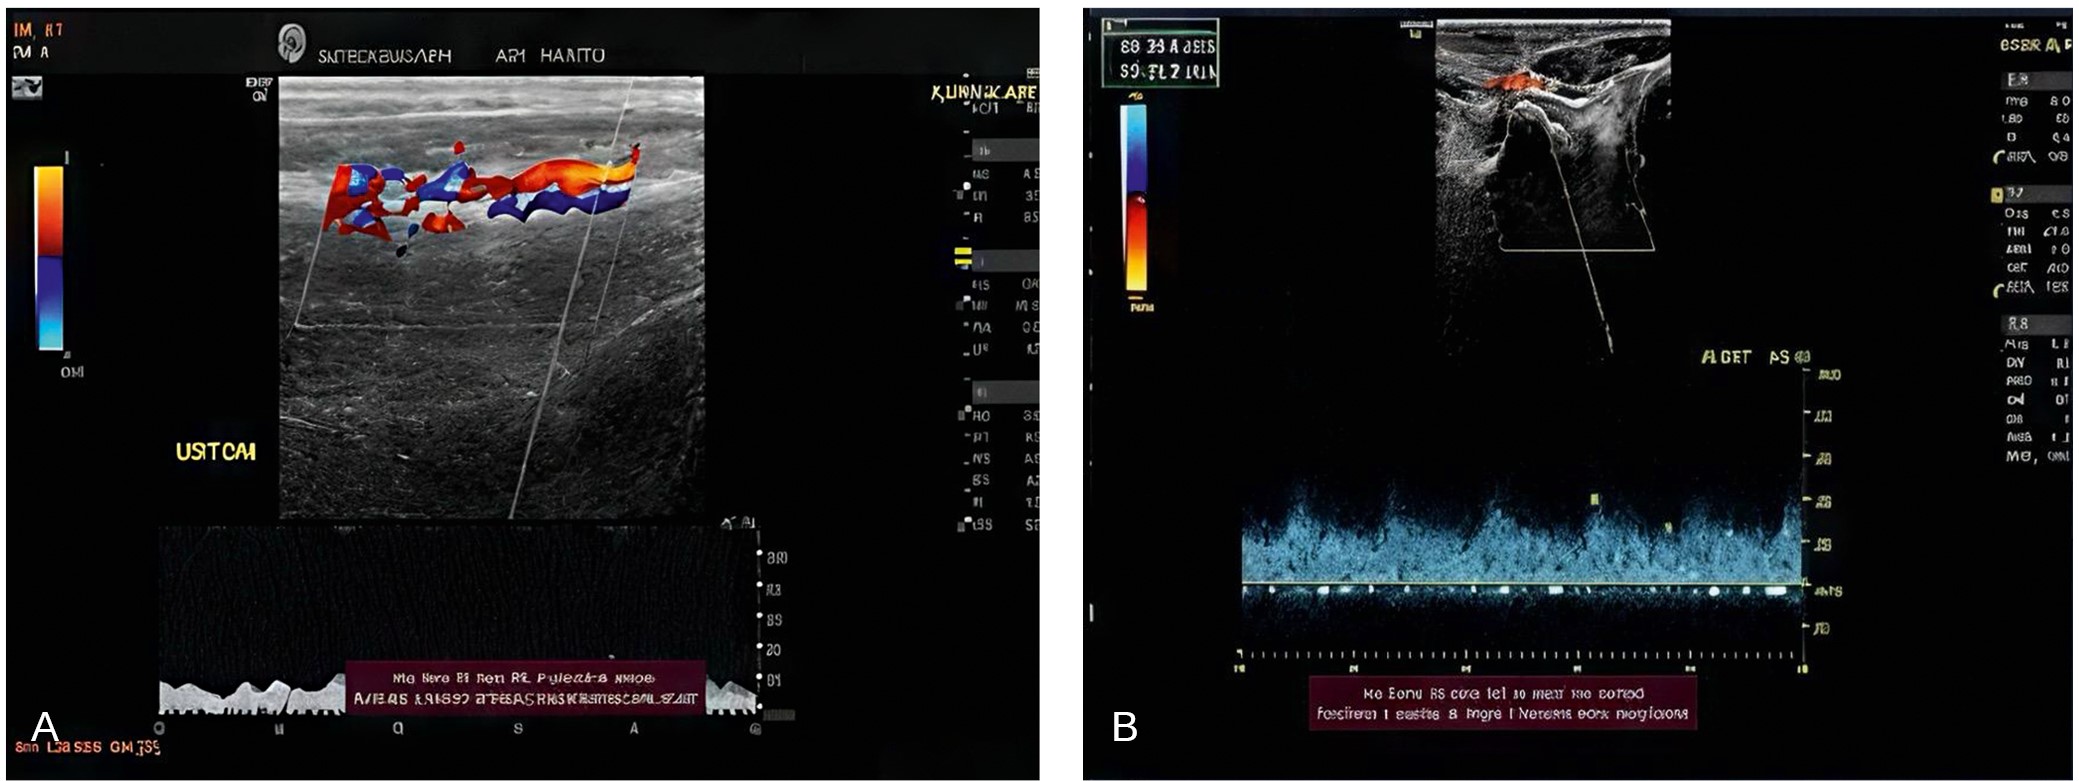

Pathology is detected and assessed directly using duplex ultrasound (US) (a General Electric Logic P6 machine equipped with a linear probe with 7.5–12 MHz frequency and a curvilinear probe with 2.5–7.5 MHz frequency), which uses color, grayscale, and spectral Doppler ultrasound [20]. Color Doppler pinpoints the degree of illness more accurately and efficiently, whereas spectral Doppler is quantitative. Experienced vascular scientists examined an individual in a horizontal position with a portable US system equipped with a 5–10 MHz linear array, using imaging, color, and pulsed Doppler modes. The aortoiliac, femoral, popliteal, and pedal parts were all scanned throughout the assessment [21] as seen in Figure 1.

Fig. 1. A — depicts Doppler scanning of the dorsalis pedis artery in a peripheral arterial disease patient with intermittent claudication prior to intervention; B — indicates an improvement in both peak systolic velocity and acceleration time following 12 weeks of supervised treadmill training with TENS

To confirm a PAD case, one of the following requirements must be met: (1) at least one narrowing of more than 50 %. (2) a blockage, or (3) extensive stenosis to the point where circulation was impeded and the waveform was reduced in the popliteal area. A typical Doppler waveform contains three distinct triphasic features: a visible upward systolic peak, a little negative early diastolic wave, and a slightly positive late diastolic wave. When PAD is present, Doppler waves might be biphasic or monophasic [20].